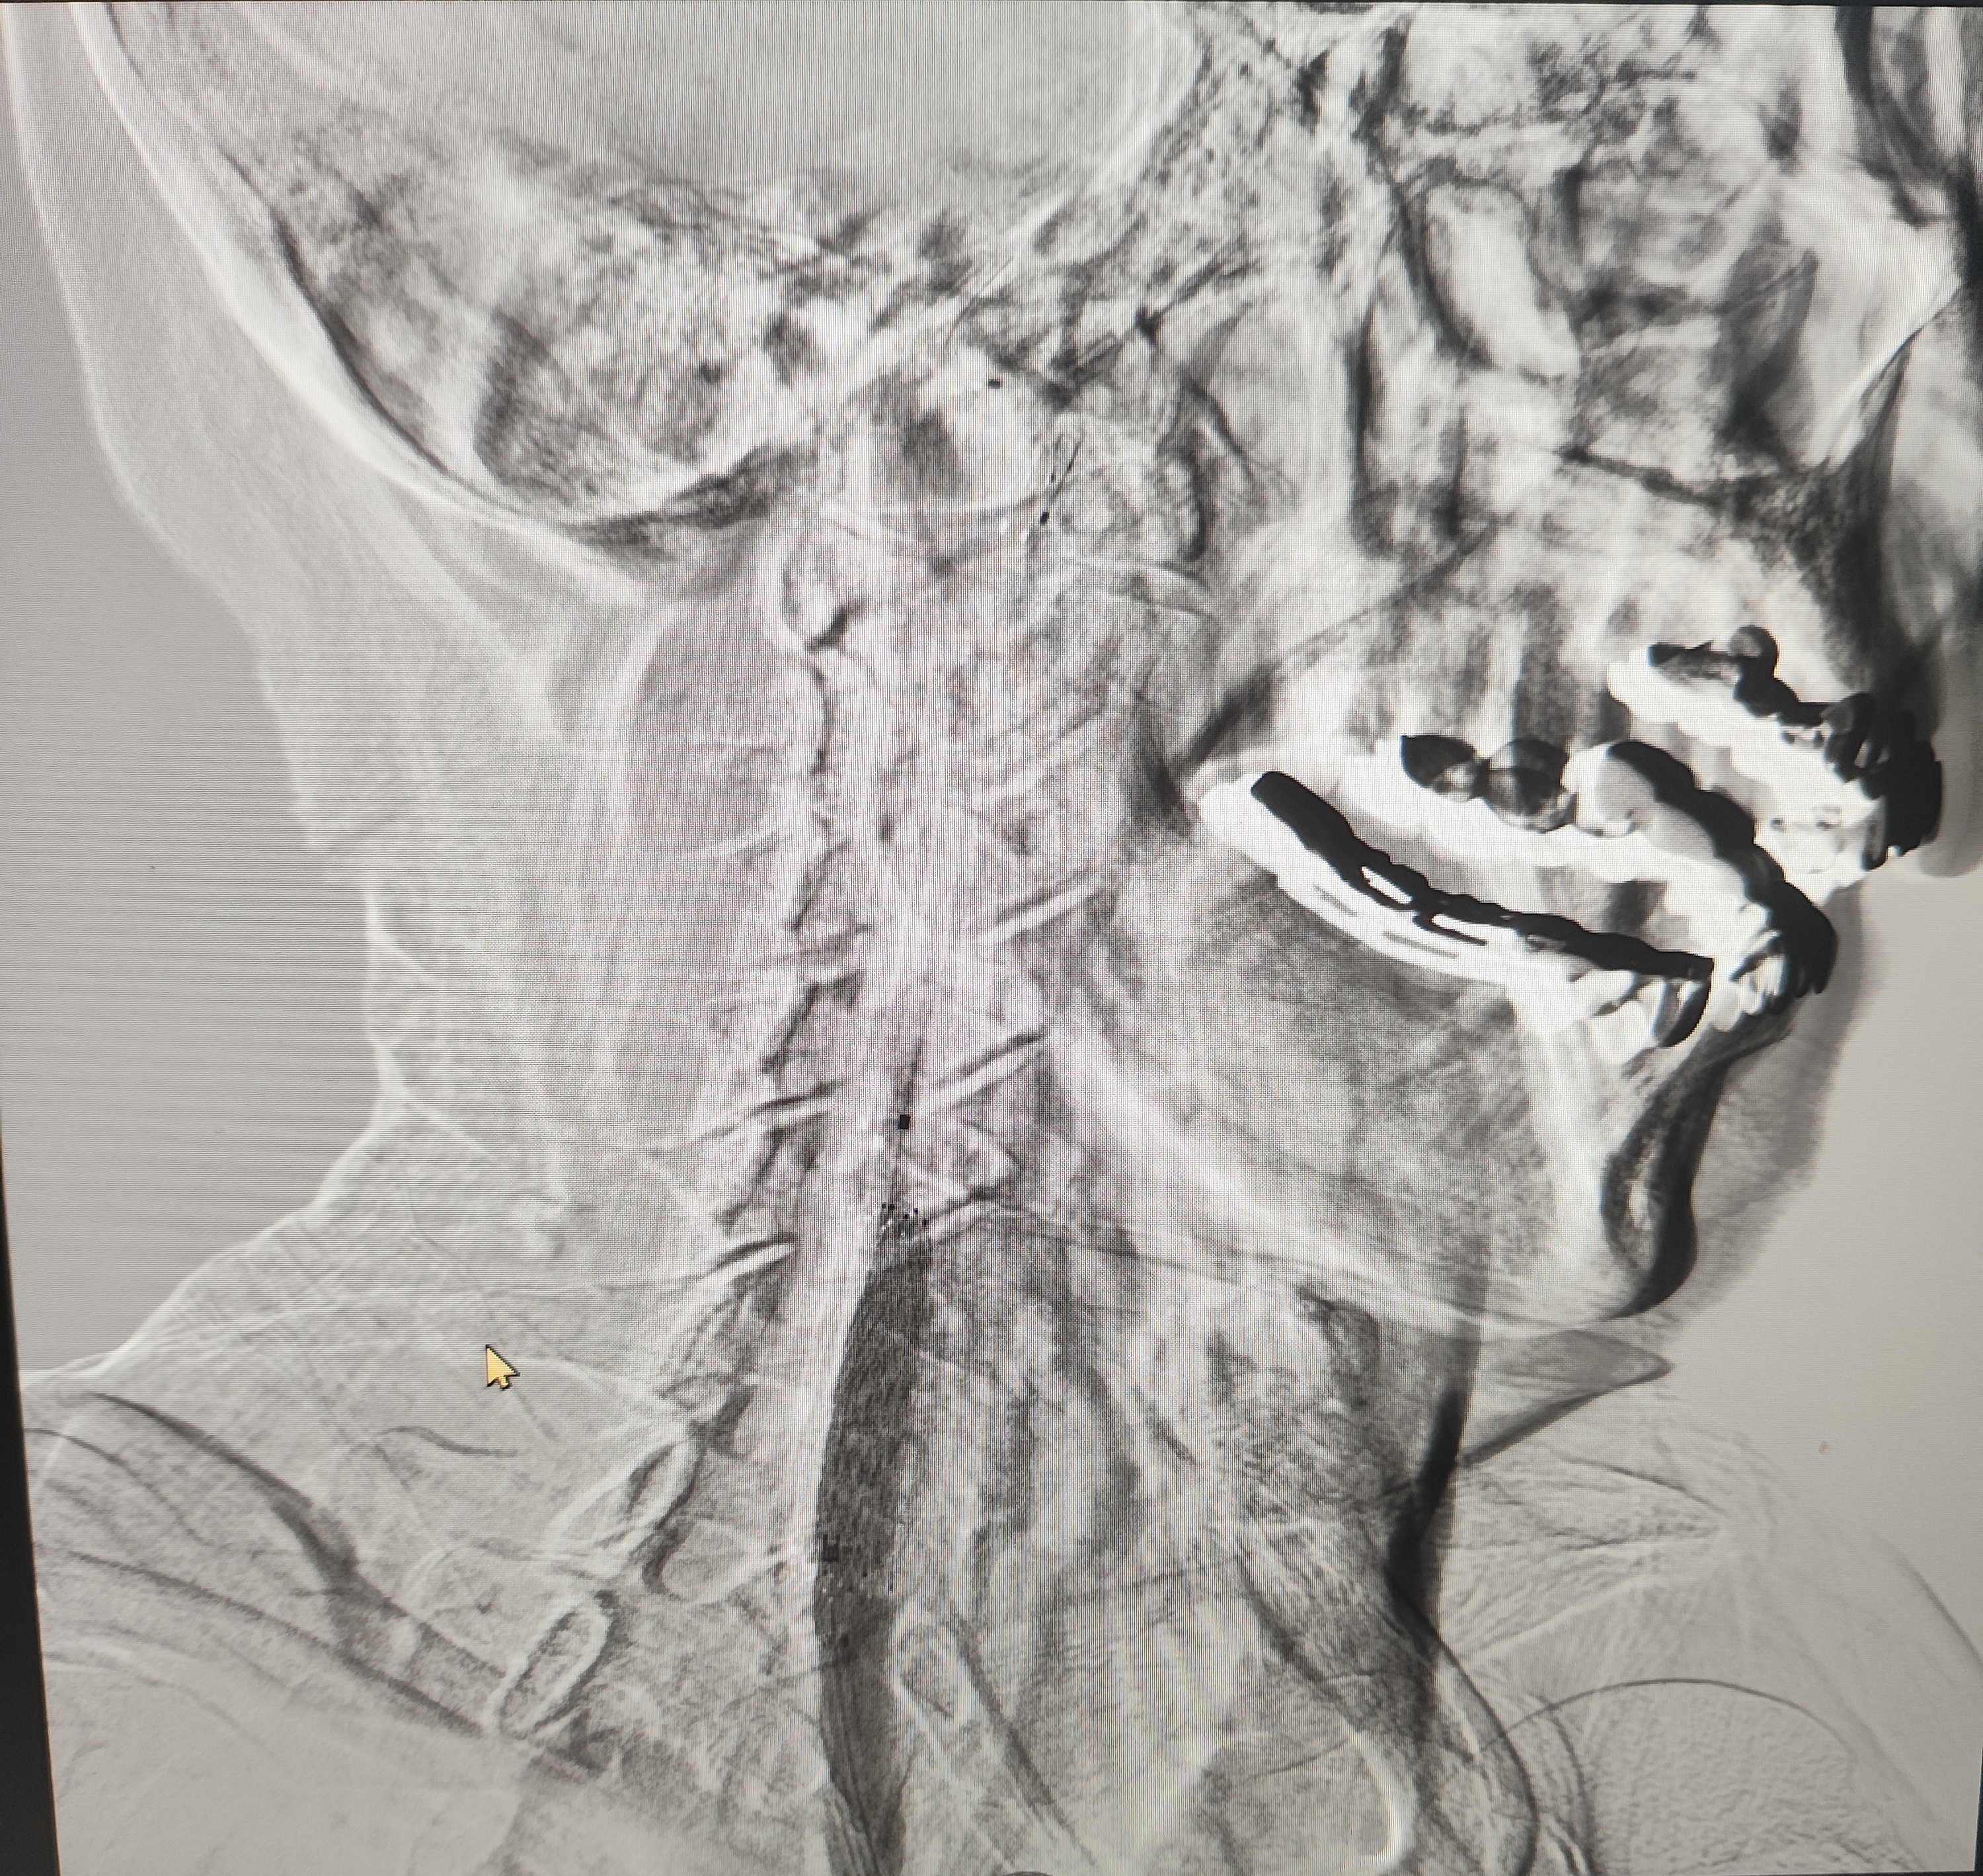

颈总巨大斑块急性闭塞的血管内治疗(双颈动脉支架桥接+支架释放后掉斑块,抽吸取栓)

84岁男性,既往右侧颈动脉狭窄病史8个月,多次脑梗未治疗,本次突发左侧肢体无力来诊,发病30小时后转入我院。

症状进行性加重,意识逐渐模糊,烦躁,左上肢肌力1级,左下肢肌力2级,当地考虑开通难度大,转入我院。

急诊上台。